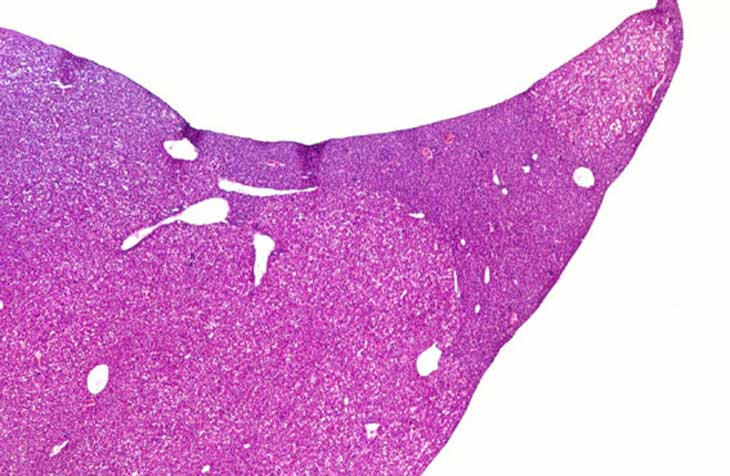

An aged uPA transgenic mouse with an hepatocellular adenoma. There is evidence of toxic hepatopathy in the adjacent hepatic parenchyma.